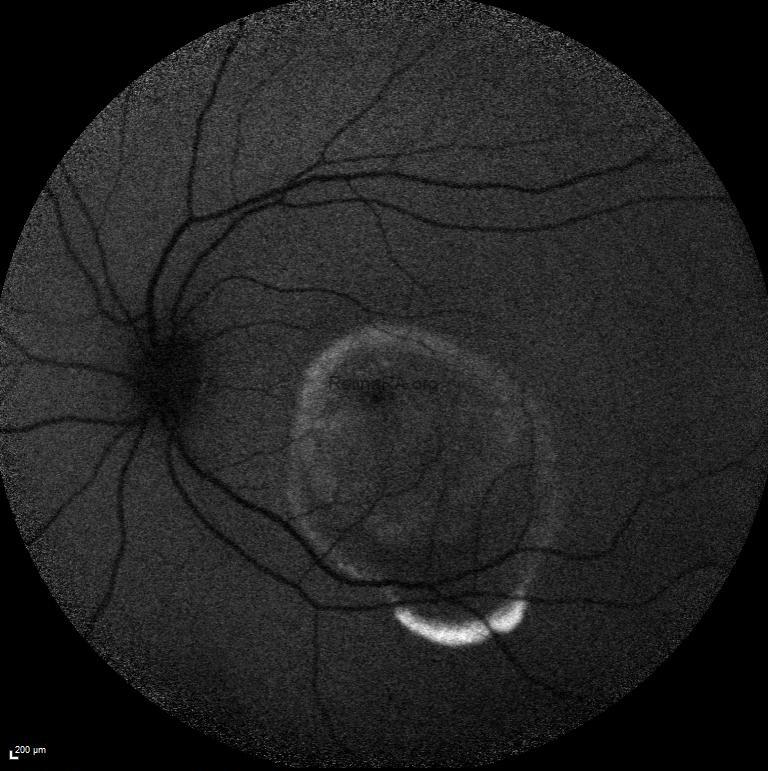

Fundus autofluoresence of both eyes showed symmetrical hypoautofluorescence with a rim of hyperauotofluorescence extending into the inferior macula of both eyes.